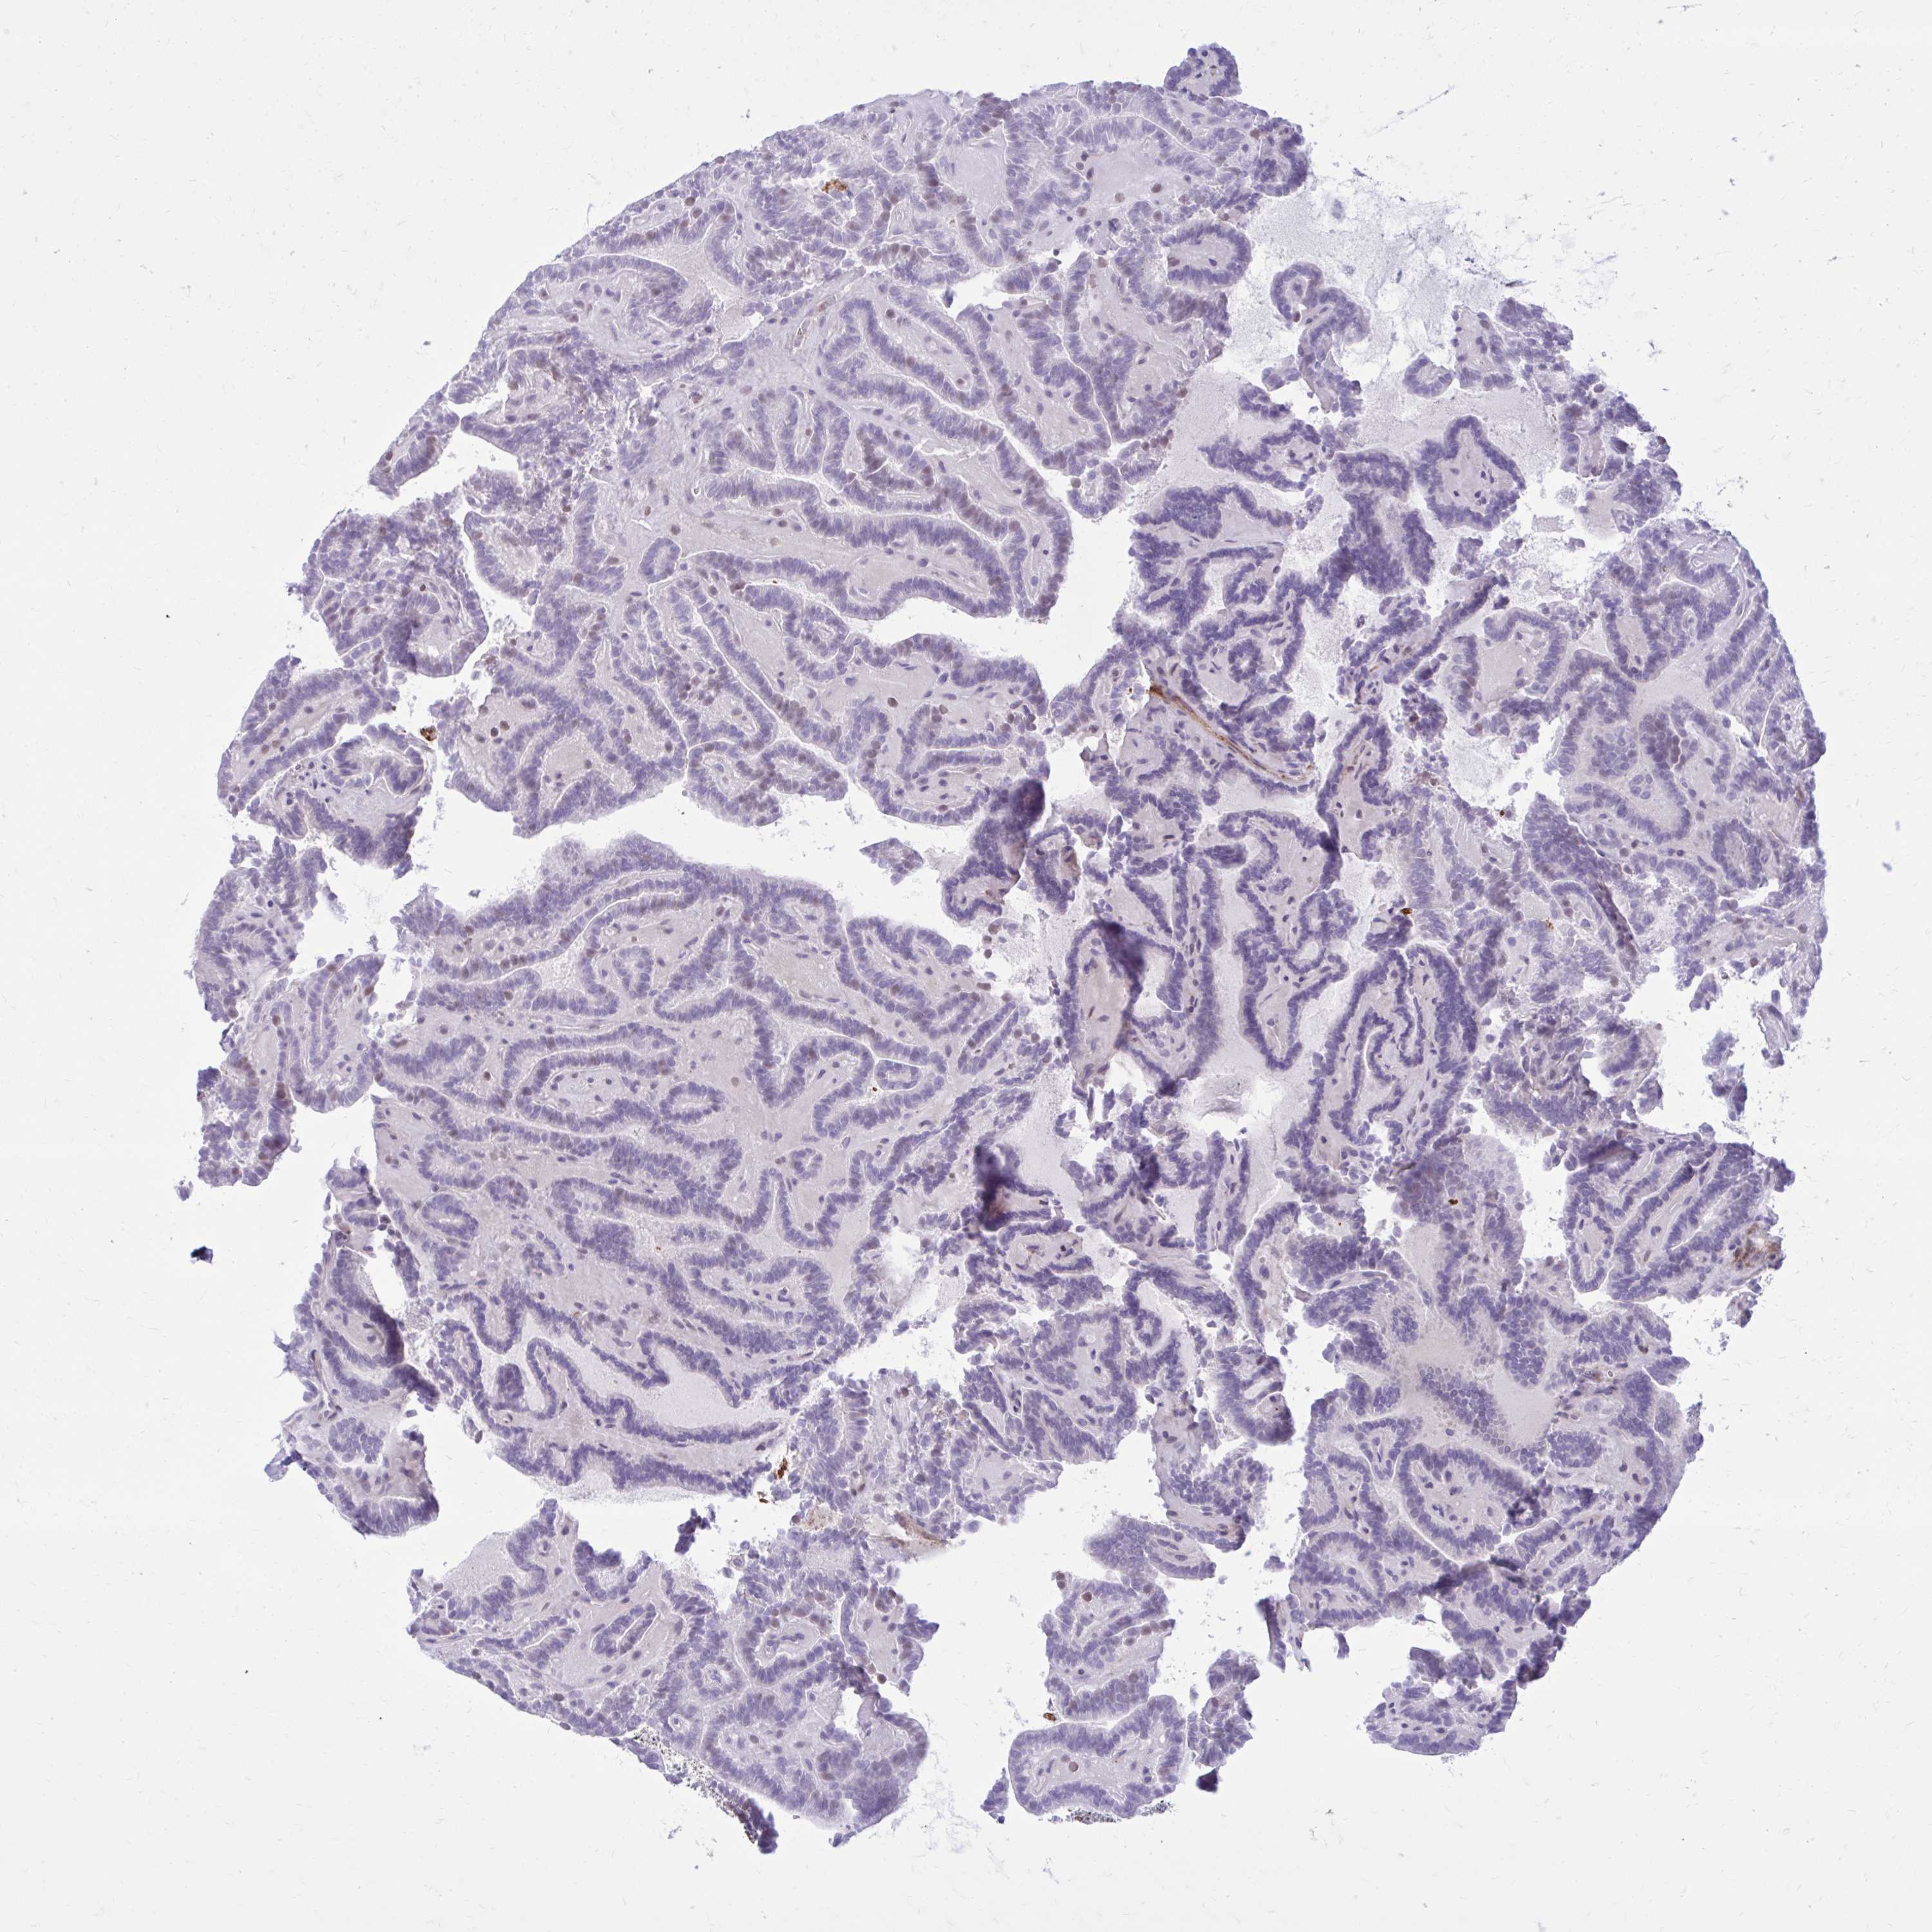

THYROID CANCER - Protein expressioni

A mouse-over function shows sample information and annotation data. Click on an image to view it in a full screen mode. Samples can be filtered based on level of antibody staining by selecting one or several of the following categories: high, medium, low and not detected. The assay and annotation is described here.

Note that samples used for immunohistochemistry by the Human Protein Atlas do not correspond to samples in the TCGA dataset.

Antibody stainingi

Antibody staining in the annotated cell types in the current human tissue is reported as not detected, low, medium, or high, based on conventional immunohistochemistry profiling in selected tissues. This score is based on the combination of the staining intensity and fraction of stained cells.

Each image is clickable and will lead to virtual microscopy that enables deeper exploration of all samples and also displays staining intensity scores, fraction scores and subcellular localization as well as patient and tissue information for each sample.

Antibody HPA054347

Antibody HPA058007

Staining

High

Medium

Low

Not detected

Intensity

Strong

Moderate

Weak

Negative

Quantity

>75%

75%-25%

<25%

None

Location

Nuclear

Cytoplasmic/membranous

Cytoplasmic/membranous,nuclear

Papillary adenocarcinoma, NOS

Follicular adenoma carcinoma, NOS